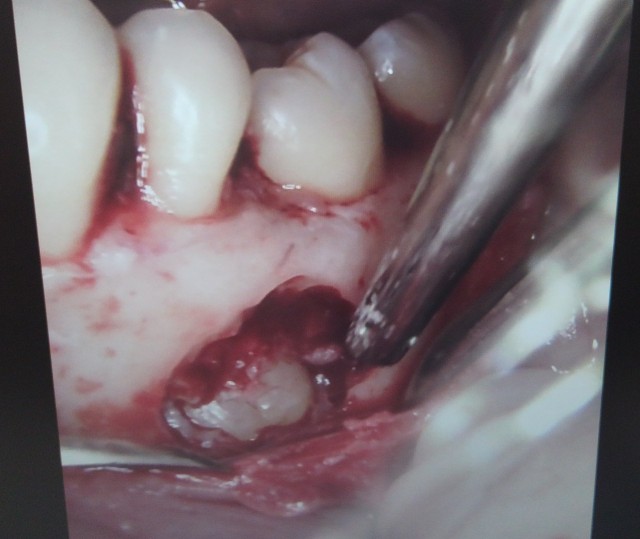

オトガイ孔と神経を見えるように慎重に歯茎を開けてゆきます。

オトガイ孔移動術によって神経損傷の可能性をまず低くします。

骨を削り、含歯性嚢胞を出してゆきます。

嚢胞の上部をとると中から埋伏歯が出てきます。

歯の頭を落とします。

その隙間から残った歯の根を除去していきます。

止血して縫いましょう。